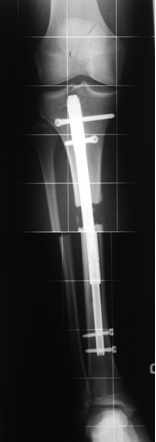

Teleskopnagelung in der Osteogenesis imperfecta-Behandlung

Bei der operativen Behandlung steht die Versorgung von Knochenbrüchen oder Achsfehlstellungen mit Teleskopnagelungen im Vordergrund. Aus orthopädischer Sicht ist trotz ständiger Bruchgefahr viel Bewegung wichtig, um eine stützende Muskulatur aufzubauen und Skelettveränderungen vorzubeugen bzw. zu verzögern.